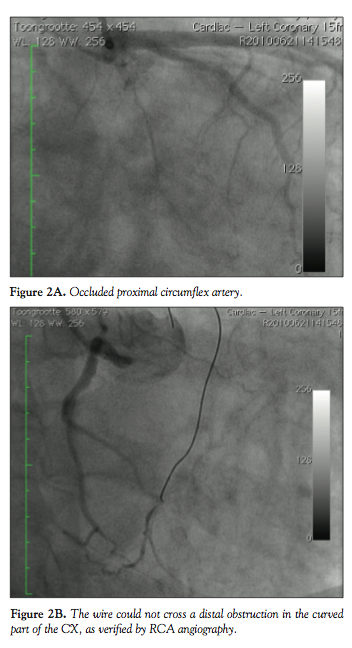

Patient #2. A 56-year-old male patient was admitted for PCI of a CTO of the proximal left

circumflex (CX) coronary artery (Figure 2A). The distal CX was collaterally filled by the RCA. PCI was performed via RRA with a 6 Fr Kimny guide. Multiple attempts to cross the lesions with several wires (Asahi Miracle 3, Miracle 6 and Confianza) failed. Contralateral injections of the RCA showed that the tip of the wire could not cross the very distal part of the long occlusion (Figure 2B). Attempts to perforate the occlusion by increasing support with a Finecross and with a 1 mm over-the-wire balloon also failed.